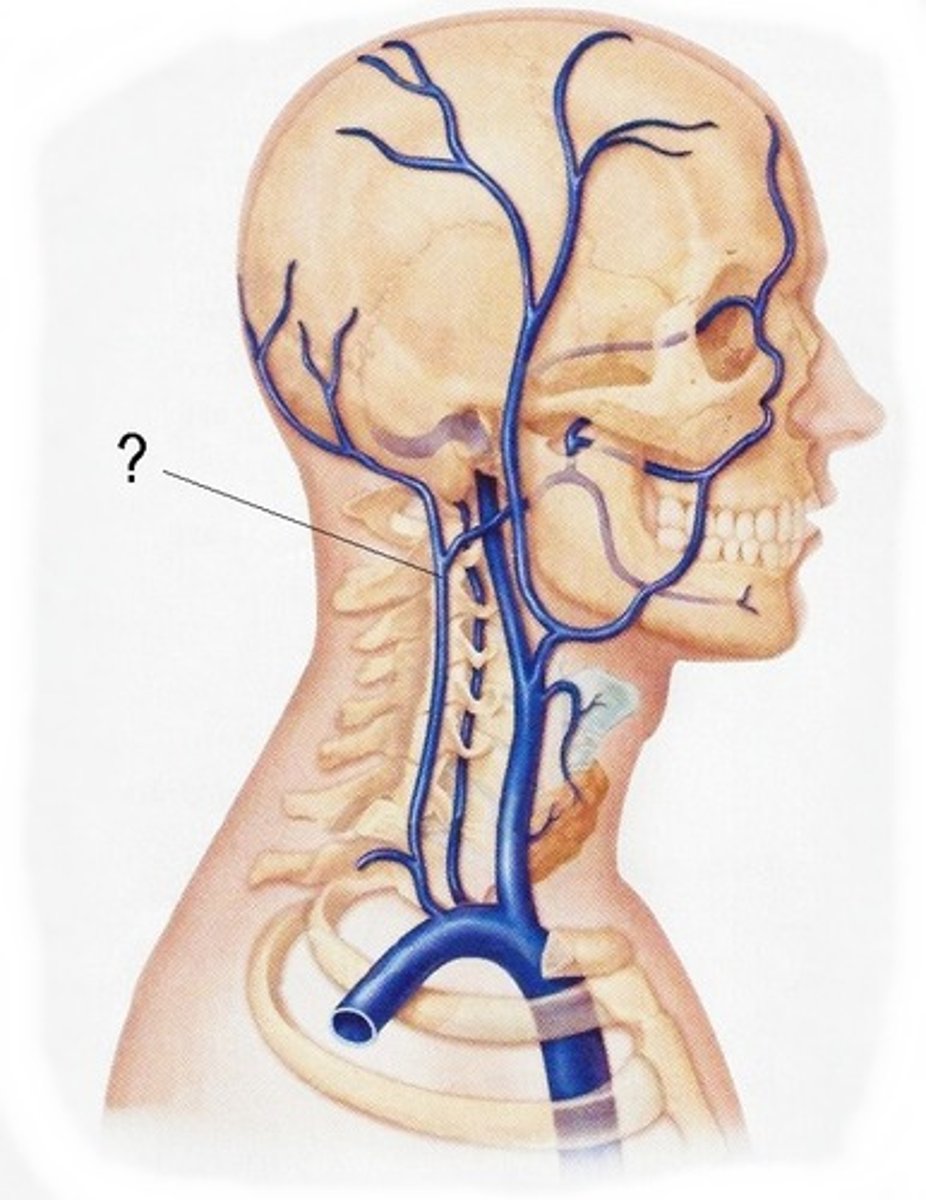

jugular veins

brachiocephalic vein

subclavian vein

superior vena cava